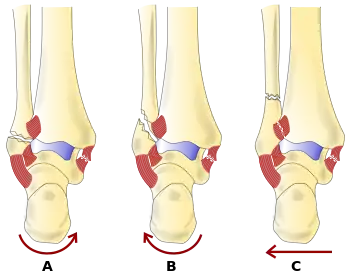

The Danis–Weber classification (often known just as the Weber classification) is a method of describing ankle fractures. It has three categories:[1]

- Type A

Fracture of the fibula distal to the syndesmosis (the connection between the distal ends of the tibia and fibula). Typical features:

- below level of the ankle joint

- tibiofibular syndesmosis intact

- deltoid ligament intact

- medial malleolus occasionally fractured

- usually stable: occasionally nonetheless requires an open reduction and internal fixation (ORIF) particularly if medial malleolus fractured

- Type B

Fracture of the fibula at the level of the syndesmosis. Typical features:

- at the level of the ankle joint, extending superiorly and laterally up the fibula

- tibiofibular syndesmosis intact or only partially torn, but no widening of the distal tibiofibular articulation

- medial malleolus may be fractured or deltoid ligament may be torn

- variable stability

- Type C

Fracture of the fibula proximal to the syndesmosis. Typical features:

- above the level of the ankle joint

- tibiofibular syndesmosis disrupted with widening of the distal tibiofibular articulation

- medial malleolus fracture or deltoid ligament injury present

- unstable: requires ORIF

Categories B and C imply a degree of damage to the syndesmosis itself (which cannot be directly visualised on X-ray). They are inherently unstable and are more likely to require operative repair to achieve a good outcome. Type A fractures are usually stable and can be managed with simple measures, such as a plaster of paris cast.